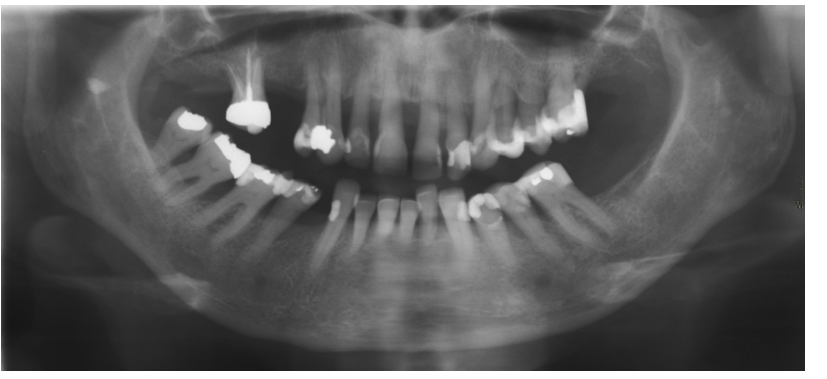

Bildexempel panoramabild

Icke-avbländad

Avbländad

Många gånger är man mest intresserad av tänderna och behöver inte avbilda hela käkarna. På de flesta panoramamaskiner finns möjligheten av avblända bilden och på så sätt reducera stråldosen. Här ovan ses ett dentalt panorama. Ofta finns också möjligheten att avbilda patientens ena sida.